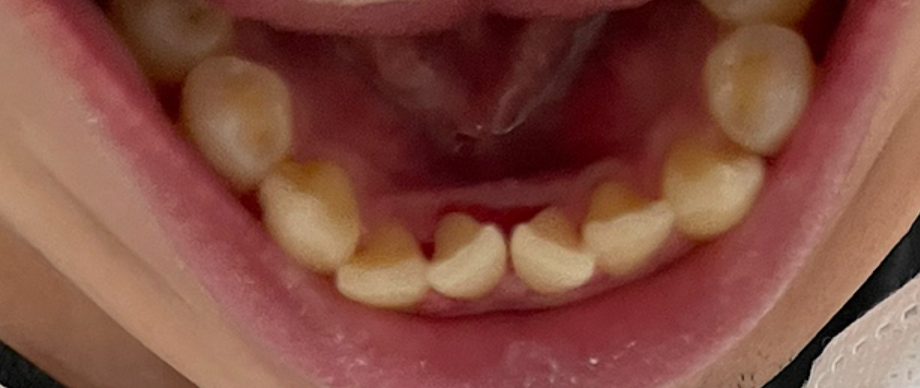

이후로 자세히 안 보고 살았는데 현재 모습입니다. 좀 누르스름 하긴 하지만 치석은 크게 쌓인 거 같지는 않네요.